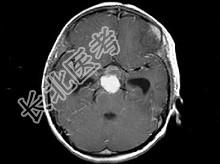

- 单项选择题男,15岁, 2个月前无明显诱因出现头痛,间断性钝痛, 根据所提供图像,最可能的诊断是 ( )

A、垂体瘤

B、颅咽管瘤(造釉细胞型)

C、生殖细胞瘤

D、胶质细胞瘤

E、结核性肉芽肿